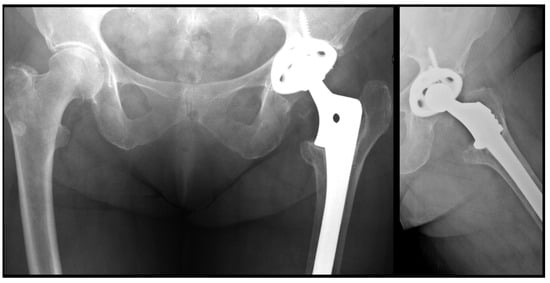

Comparison of Cylindrical and Tapered Stem Designs for Femoral Revision Hip Arthroplasty